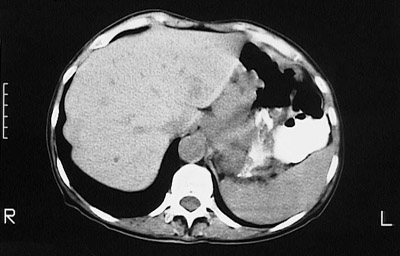

![]() | This abdominal CT scan view with contrast demontrates a mass lesion distorting the lower esophagus and upper gastric fundus, which proved to be a squamous cell carcinoma arising in the lower esophagus. It is often difficult to tell if an adenocarcinoma at this site arose in the lower esophagus or upper stomach. |